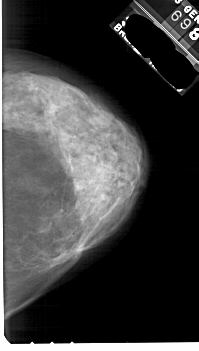

A_1844_1.LEFT_CC

LEFT_CC LINES 5491 PIXELS_PER_LINE 3226 BITS_PER_PIXEL 12 RESOLUTION 43.5 OVERLAY

FILE: A_1844_1.LEFT_CC.OVERLAY

TOTAL_ABNORMALITIES 1

ABNORMALITY 1

LESION_TYPE CALCIFICATION TYPE PLEOMORPHIC DISTRIBUTION CLUSTERED

ASSESSMENT 4

SUBTLETY 3

PATHOLOGY BENIGN

TOTAL_OUTLINES 1

BOUNDARY